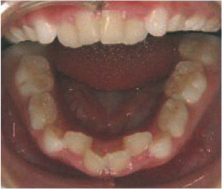

こんな歯ならびのお子様に

出っ歯

上の歯が出ている

凸凹でこぼこ

4人がけの椅子に6人座っている状態

受け口

下の歯が出ている